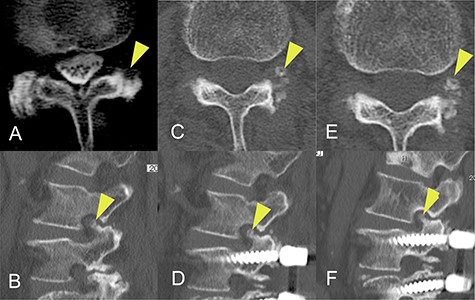

Magnetic resonance and computed tomography (CT) images acquired at the time of onset of radiculopathy. (A) Sagittal T1-weighted magnetic resonance image showing moderate foraminal stenosis at the L2–L3 level. (B) Sagittal CT image showing ossification of the ligamentum flavum protruding into the foramen. (C, D) Axial CT image showing OLF in the capsular portion. (E, F) Postoperative CT image confirming adequate removal of the ossification of the ligamentum flavum.

The patient was an 82-year-old Japanese woman who had presented 2 months earlier with pain and numbness in her left lower extremity. She had a history of vertebral fracture at L1 4 months previously for which she had been treated with a lumbar orthosis for 2 months (Fig. 1). Magnetic resonance imaging of the lumbar spine demonstrated foraminal stenosis at the L2–L3 level (Fig. 2A). CT images of the lumbar spine revealed ossification in the capsular portion of the ligamentum flavum around the L2–L3 facet joint (Fig. 2B–D). She underwent L2–L3 foraminotomy with excision of the capsular portion of the OLF. The patient’s symptoms disappeared immediately after surgery. Postoperative CT scans showed good decompression at the operated level (Fig. 2E and F).